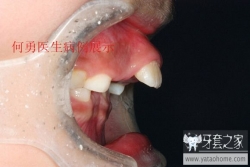

突面型,

有两种,一种是骨性的,整个上颌骨向前突出

或者下颌骨发育不足,此病例为患儿有严重的咬下唇习惯导致牙性前突,骨性下颌骨发育不良(此患者人在甘肃,关于治疗效果有后续报道)

另一种是牙性的,也就是我们常说的龅牙。